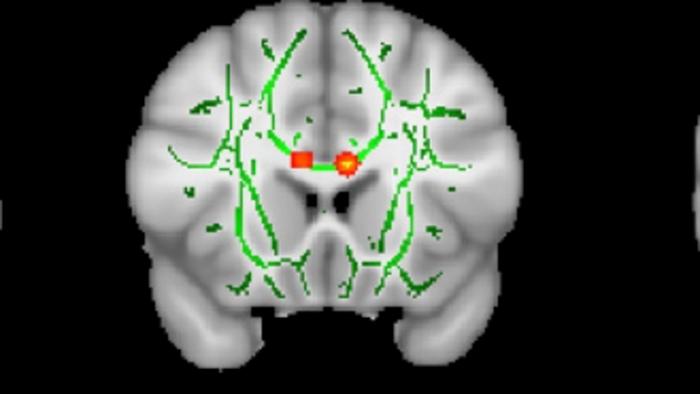

Green lines show white matter pathways. Red/yellow zones show where differences appear between the non-maltreated CD group and healthy controls. These differences are found in the main pathway connecting the two hemispheres of the brain. No differences are seen between the abused CD group and healthy controls.

- The white matter of abused youth with CD did not differ from healthy controls, but white matter of non-abused youth was significantly altered in key pathways within the brain.

The new study found differences in ‘white matter’ between individuals with conduct disorder (CD) who have been abused and those who have not. White matter represents the neural pathways along which electrical signals pass as one brain area communicates with another.

The researchers found that, unlike with grey matter, the white matter of abused individuals with CD does not differ from that of healthy controls. By contrast, youth with CD who have not been abused show significant alterations in their white matter.

The new study’s international team of researchers found a second difference between the brains of people with CD: those who have been maltreated exhibit changes in the superior longitudinal fasciculus (a white-matter pathway involved in emotion processing, learning and social cognition) when compared to their non-maltreated counterparts.